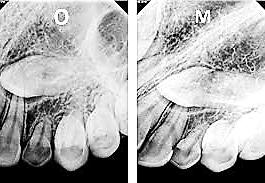

b) Análisis radiográficos, periapicales, ortopantomográficos, oclusales, lateral de cráneo, anteroposterior de cráneo.

c) Estudio y análisis tomográfico en tercera dimensión del cráneo a nivel maxilar y mandibular (Figura 24).

Al estar ausente algún germen dental (como los laterales superiores permanentes y/o premolares de ambas arcadas, “los de mayor incidencia”),10 se inhibe la estimulación adecuada en el desarrollo óseo de esa zona específica, ya que al no existir el germen dental, la matriz ósea inhibe su crecimiento en esas zonas en específico11 (Figura 29).

Diagnóstico y tratamiento ortodóntico interceptivo como prevención en la inclusión del canino

maxilomandibulares, 17 las cuales propician alteraciones en el proceso del intercambio dentario; en la que una reducción de los espacios necesarios para el acomodo de los caninos y de otros órganos dentales en las arcadas, retrasa e impide que el impulso natural propio de la formación radicular como empuje fisiológico, impidiendo el desplazamiento y la erupción del canino en tiempo y una posición ideal dentro del arco dental (Figura 30).

Sumado a lo anterior, la retención generada dentro del macizo óseo basal altera su posición en angulación y dirección correcta de erupción. Situación que en ocasiones daña las raíces de los dientes adyacentes al canino y que finalmente podrá quedar incluido, en el peor de los casos, cuando no encuentra una salida de emergencia hacia el paladar o el vestíbulo12 (Figura 31).

La formación de caries en la dentición decidua y la consecuente pérdida prematura de órganos dentales deciduos, en algunas ocasiones, son

consideraciones a tomar muy en cuenta como factor etiológico en la inclusión del canino (Figura 32).

Por un lado, la presencia de caries interproximales en dientes deciduos, ya sea de manera independiente o como consecuencia de caries rampantes en uno o varios dientes, propicia la disminución de la longitud y/o perímetro del arco dental, donde ya no habrá, en consecuencia, el espacio necesario para el acomodo definitivo de los caninos y premolares permanentes.14

Por otro lado, al haber una pérdida prematura de un diente deciduo, además de generar una disminución de la longitud del arco dental, la biomecánica fisiológica propia de nuestro organismo, tiende a cerrar los espacios o brechas generadas por la pérdida de algún órgano dental, mesializando los dientes distales al diente faltante y generando extrusión del antagonista inmediato (Figura 33).

Figura 29.

Figura 30.

Figura 31.

Figura 32.